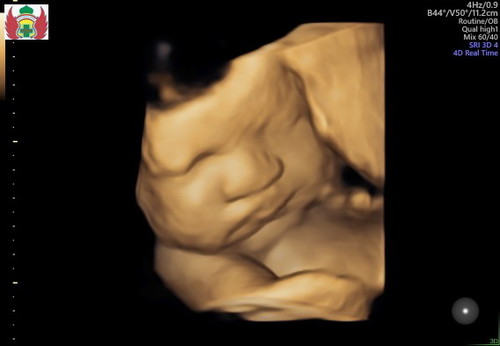

Ini usia 29wekk terakhir usg 4D. senin mau usg 4D lagi usia 34week perkiraan